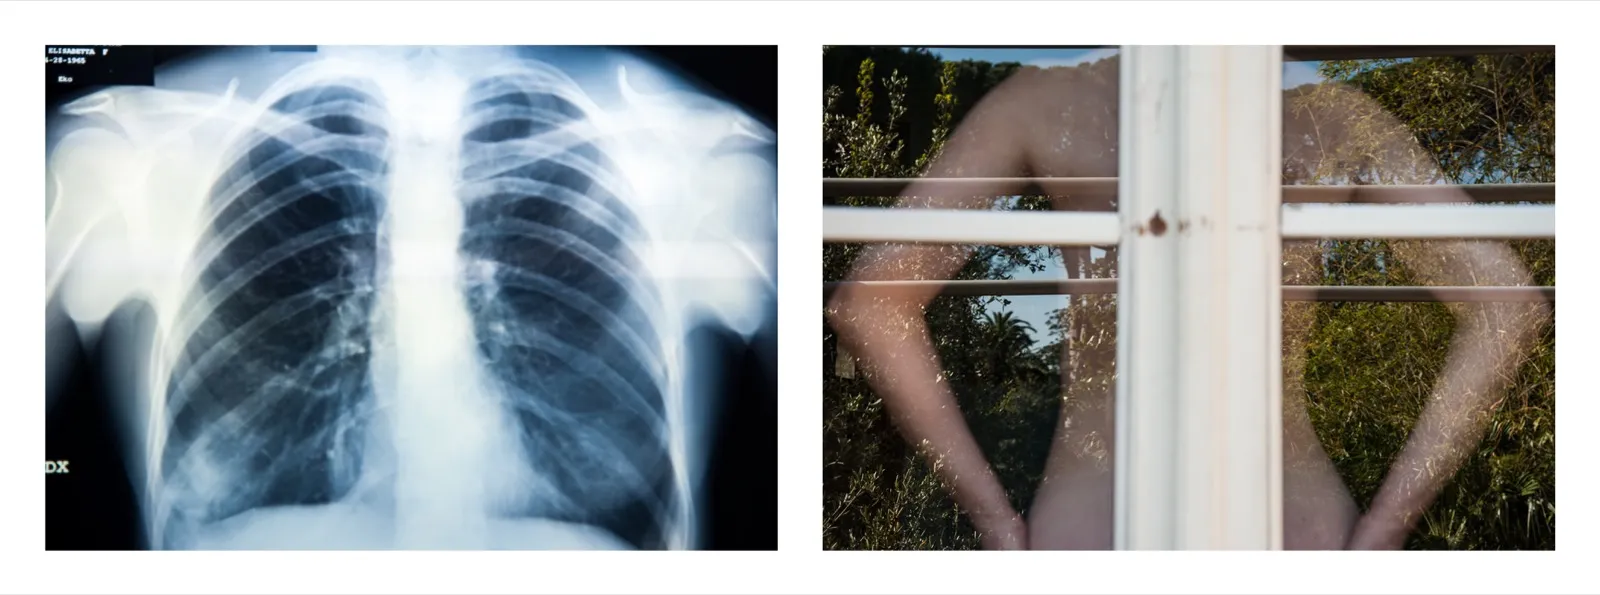

L’incipit del lavoro è costituito dall’immagine radiografica del teschio, la cui osservazione ha consentito allo sguardo di creare una relazione mutevole tra gli spazi, avvalendosi degli elementi luce/buio e trasparenza/opacità. L’alternarsi della contemplazione del pieno e del vuoto, del luminoso e dell’oscuro ha generato una riflessione su dentro e fuori, su involucro e contenuto, in ultima analisi su vita e morte.

La messa in quadro del teschio e del volto ha implicato la creazione e l’utilizzo di una sottile linea di demarcazione che nell’atto di separare i due elementi li ha ulteriormente posti in relazione. Si è così venuta a creare casualmente – o forse causalmente – una relazione spaziale ortogonale tra gli oggetti, traducibile in un simbolo, nell’immagine frammentata di qualcosa che indugiava a manifestarsi: la porzione di una croce.

La croce è divenuta da quel momento idea dominante dello sguardo e prepotentemente anche soggetto del racconto fotografico. Laddove vita e morte instaurano un dialogo così intenso e serrato, essendo l’una ragione dell’altra, la croce diviene necessariamente figura di entrambe e dunque anche di tutti gli ingredienti di cui si compone l’esistenza: il piacere e la sua negazione, il riposo, l’attesa, la fuga, l’espiazione, la perdita ed il guadagno, la ripresa.